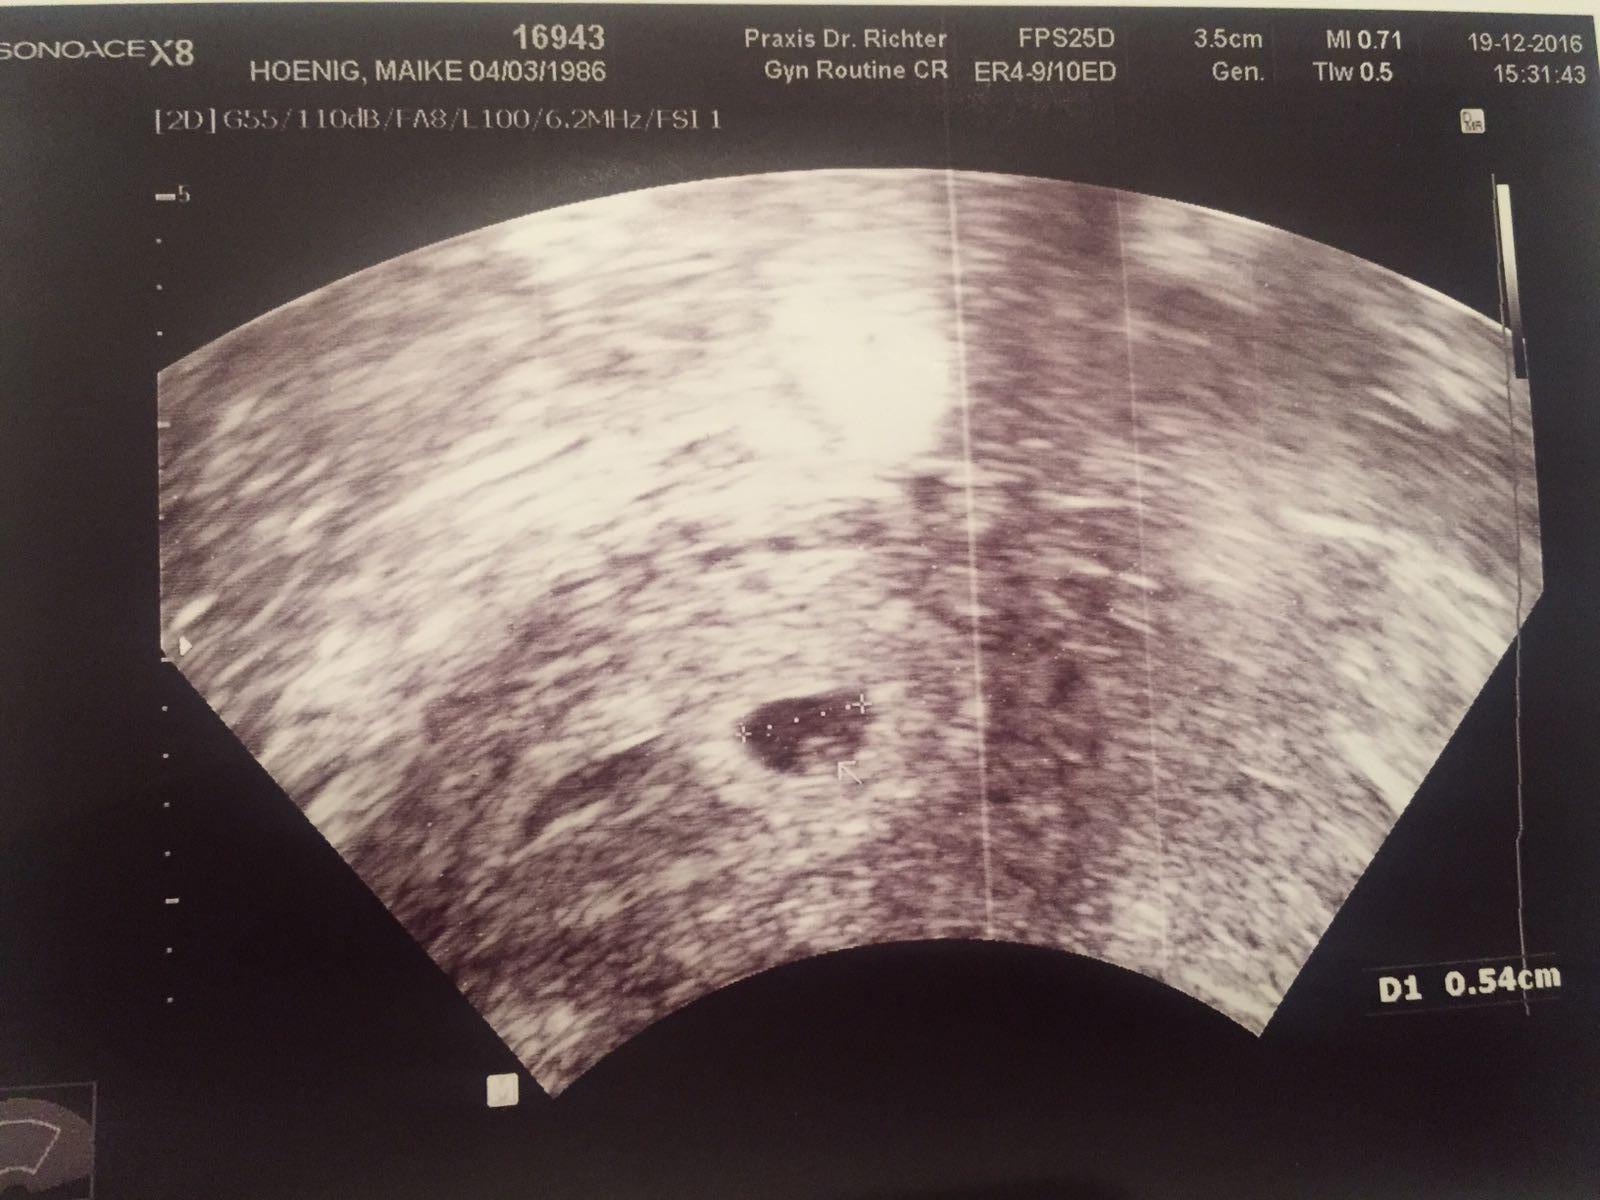

Hier nochmal ganz deutlich der Dottersack. Insgesmmt misst die Fruchthöhle 0,54 cm.

Bei Ultraschall stellte meine FÄ fest, dass das Ei aus dem rechten Eierstock kam, da dort fleißig ein Hormon produziert wird, dass die Schwangerschaft aufrecht erhält.

Außerdem habe ich eine nach hinten gekippte Gebärmutter. Fand sie interessant, da dass woh nicht so oft vorkommt, macht aber effektiv keinen Unterschied.